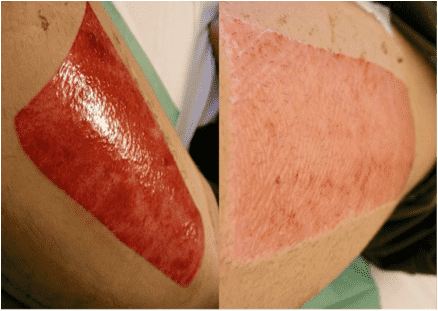

Beispiel 1:

Spalthautspenderstelle am selben Patienten: Rechtes Foto – mit Regentrix® erfolgt die Heilung in 7 Tagen.

Linkes Foto – mit konventioneller Wundbehandlung erfolgt die Heilung in 14 Tagen.